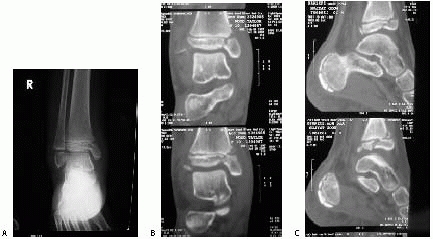

![]() |

FIGURE 26-35 A.

Severe ankle injury sustained by an 8-year-old involved in a car accident. The anteroposterior view in the splint does not clearly show the Salter-Harris type IV fracture of the tibia. The dome of the talus appears abnormal. B. CT scan shows the displaced Salter-Harris type IV fracture of the medial malleolus and a severe displaced intra-articular fracture of the body of the talus. C,D. Open reduction of both fractures was performed, and Herbert screws were used for internal fixation. (Courtesy of Armen Kelikian, MD.) |